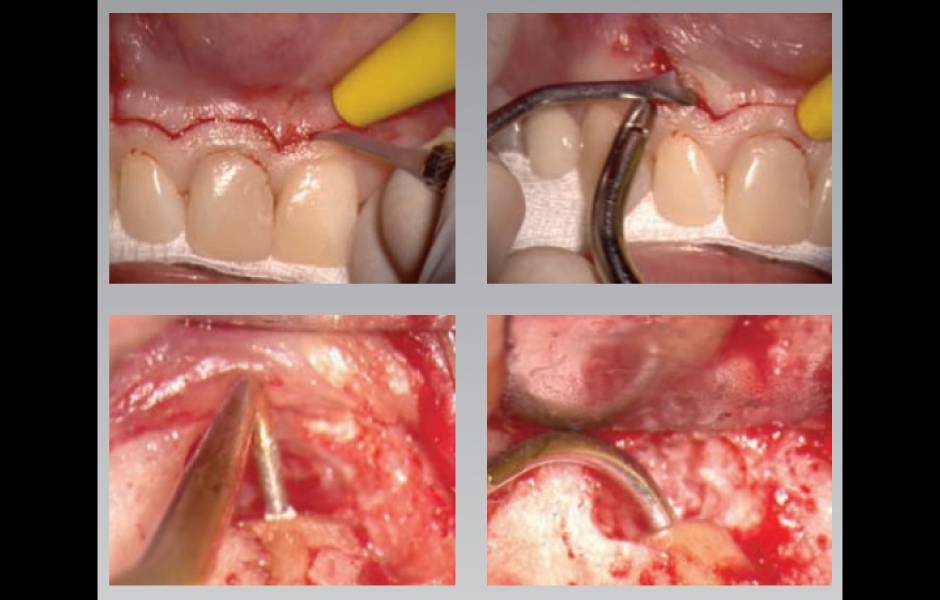

Součástí programu je také výjimečně intenzivní celodenní hands-on kurz endodontické mikrochirurgie. Nejintenzivnější praktický kurz, který byl u nás v tomto oboru organizován, si klade za cíl účastníky doslova vyždímat na retrográdním mikrochirurgickém ošetření až čtyř (!) reálných zubů, od řezáků až po horní i dolní moláry. Cílem organizátora je udělat z hands-on kurzu nezapomenutelný intenzivní zážitek, pro který nemusíte jezdit až do Florencie.

Teoretický koncept prediktabilní mikrochirurgické endodoncie od A do Z, výjimečně intenzivní hands-on kurz s operačním mikroskopem a na skutečných zubech včetně molárů.

Dr. Castellucciho přístup k mikrochirurgické endodoncii je přímočarý a čistý

…a přináší bezpečné a prediktabilní výsledky v podobě úspěšného hojení

Na přihlášené čeká opravdu intenzivní celodenní mikrochirurgický hands-on